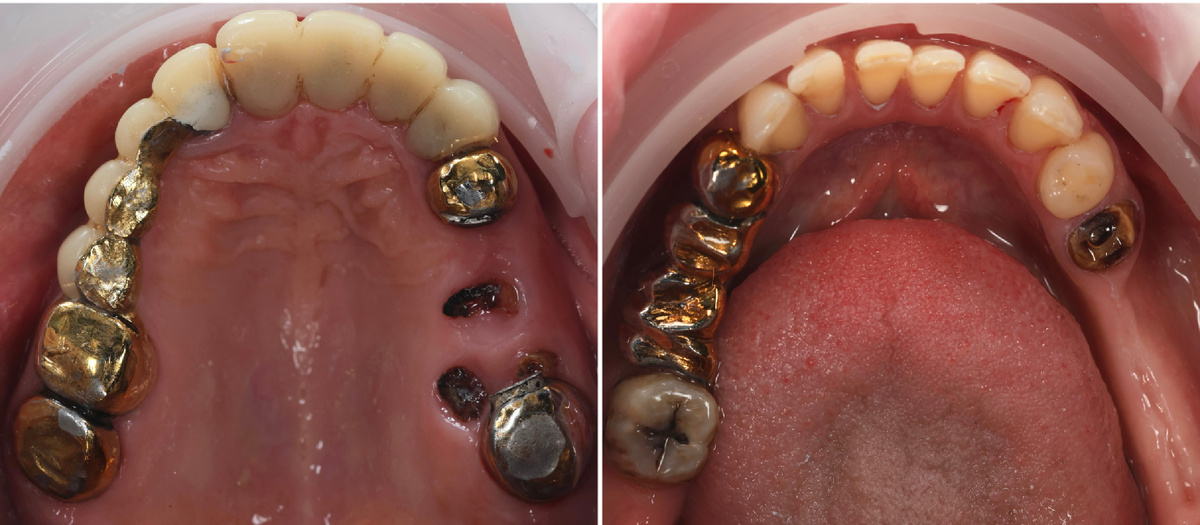

Когда пациентка пришла на первичную консультацию, то картина была такой, что один из вариантов лечения звучал как "хирургическо-ортопедический тотал" - удалить всё и начать с нуля на имплантатах.

Состояние до лечения

Но пациентке ещё нет и 50 лет. Зубов, которые можно сохранить, заморочившись с каналами, восстановлением и коронками - достаточно много. Да, это сложно, долго и дорого. Но путь был выбран именно этот - спасаем родное.

Уже больше года идёт планомерная работа - терапевтическая подготовка, хирургия, ортопедия, имплантация. Третий сегмент (нижняя челюсть, левая сторона) восстановлен, там уже стоят коронки на имплантах.

Во рту у пациентки находится много старых мостовидных протезов. Металлические штампованные коронки, несостоятельное краевое прилегание, зазоры между коронкой и зубом, в которые годами проникали микробы и слюна. Под каждой такой коронкой - своя жизнь кипит и своя история разрушения ей присуща.